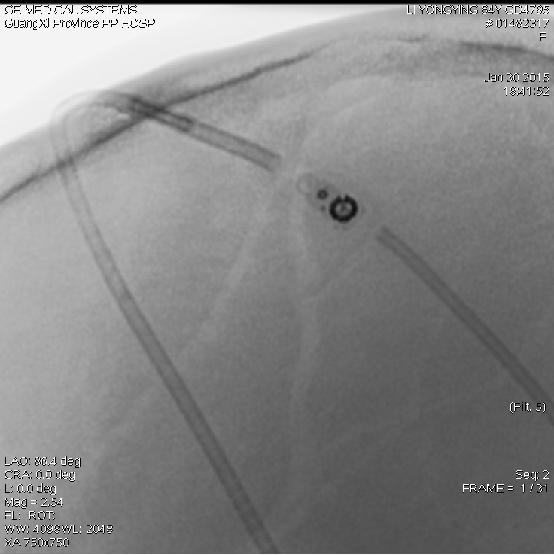

2015-1-30 DSA

2015-2-10 X线

再次呕吐3天;面部头痛有所缓解(卡马西平)。

调压200